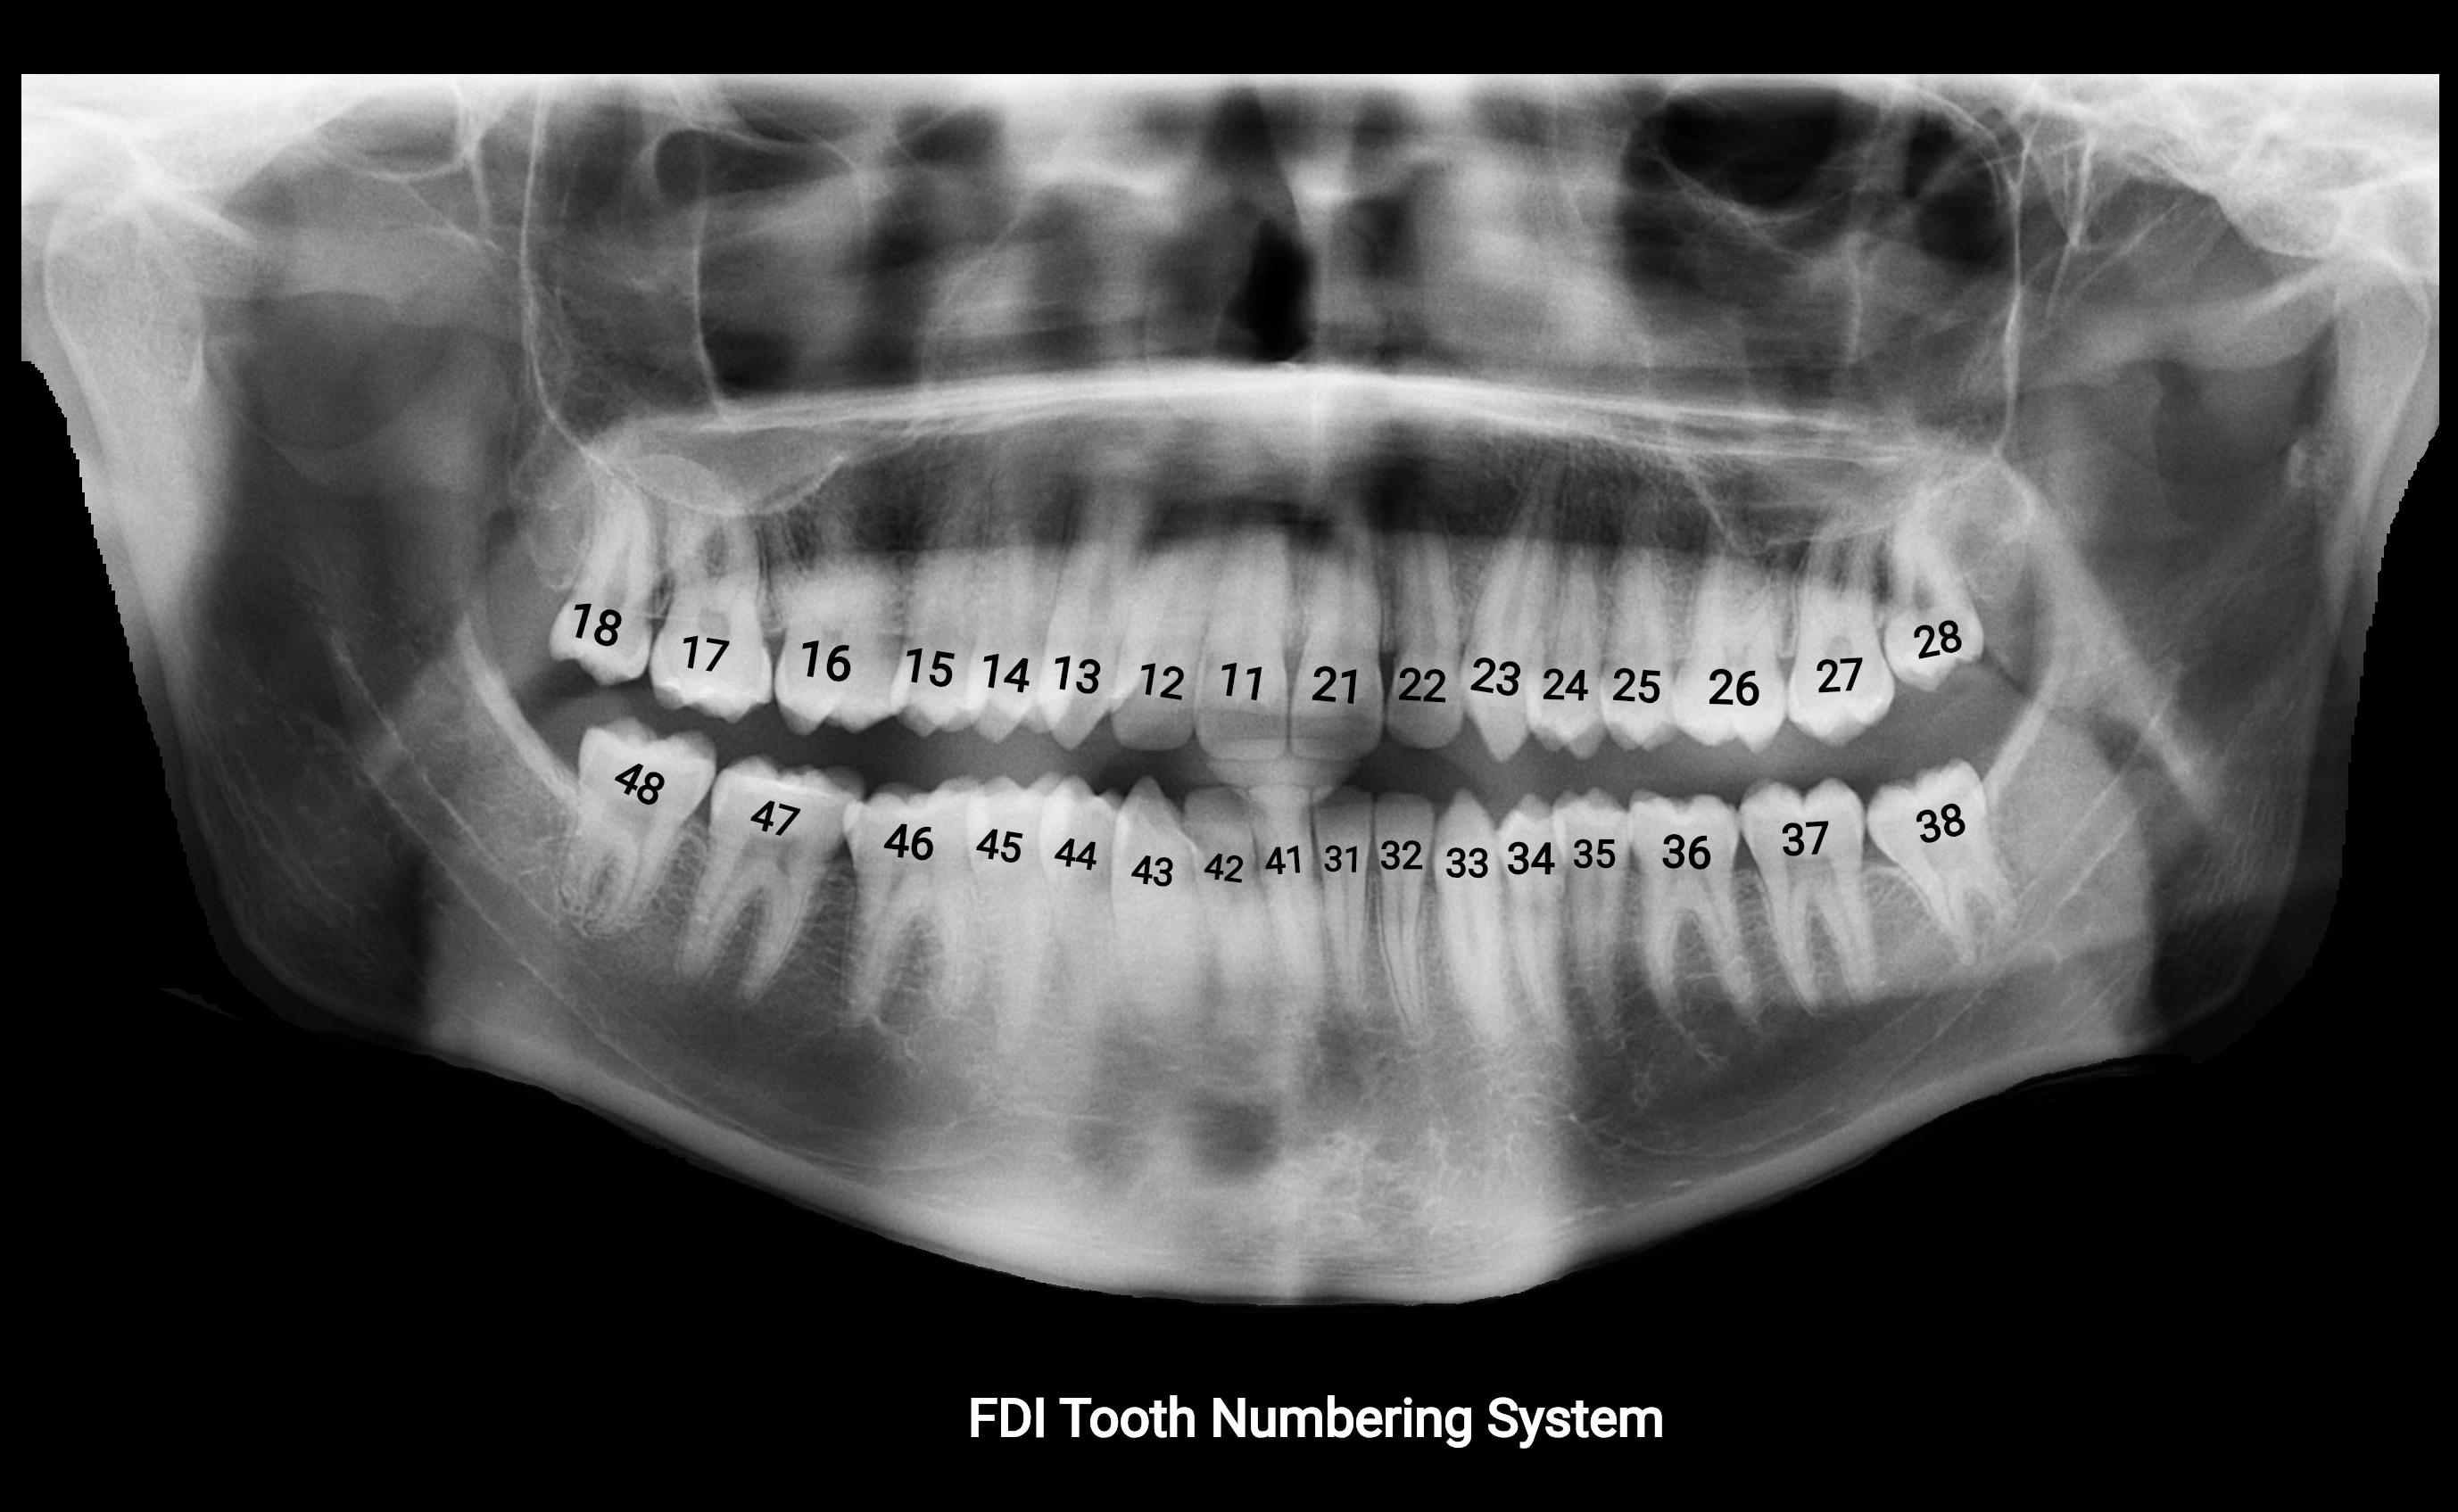

Alveolar process of maxilla

The alveolar process of the maxilla is the bony ridge of the maxilla that houses the upper teeth, extending from the anterior nasal spine to the maxillary tuberosity posteriorly. It consists of compact cortical bone on its outer surfaces and trabecular (cancellous) bone internally, with alveolar sockets (dental alveoli) forming individualized cavities for each tooth. The alveolar process develops in association with tooth eruption and resorption, adapting its shape and volume throughout life. It also forms part of the hard palate medially and contributes to the architecture of the midface, supporting the upper lip, cheeks, and nasal floor.

CT Appearance

• The alveolar process is clearly hyperdense cortical bone surrounding less dense trabecular bone

• Dental sockets appear as small, well-defined hypodense cavities

• Surrounding air in oral cavity or maxillary sinus appears hypodense, providing natural contrast

• CT allows excellent visualization of bone volume, cortical integrity, alveolar height, and dental alignment

• Useful for evaluating trauma, periodontal disease, dental implant planning, and congenital anomalies